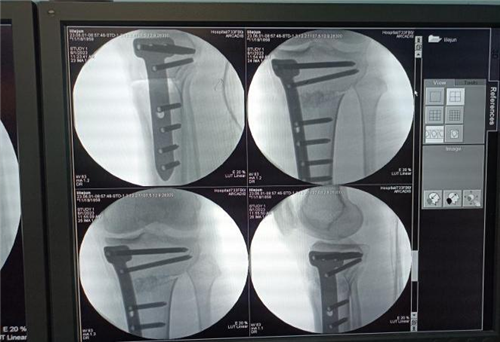

如何精准定位截骨是术者必须在术前要考虑的重点,而我院骨科手术机器人具有精准微创的独特优势,二者完美结合即可实现精准定位截骨的目的。经与患者及其家属充分沟通后,李强主任团队决定对患者实施“天玑骨科手术机器人导航辅助下胫骨结节下单平面高位截骨术”。

(术中)